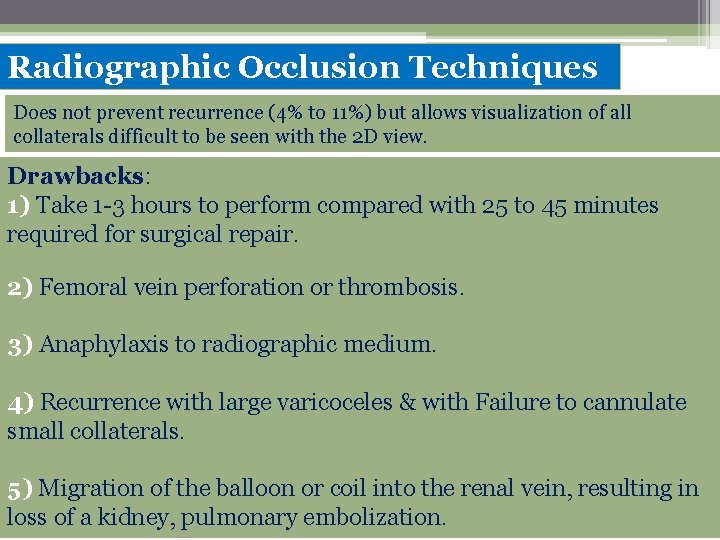

Radiographic Occlusion Techniques Does not prevent recurrence (4% to 11%) but allows visualization of all collaterals difficult to be seen with the 2 D view. Drawbacks: 1) Take 1 -3 hours to perform compared with 25 to 45 minutes required for surgical repair. 2) Femoral vein perforation or thrombosis. 3) Anaphylaxis to radiographic medium. 4) Recurrence with large varicoceles & with Failure to cannulate small collaterals. 5) Migration of the balloon or coil into the renal vein, resulting in loss of a kidney, pulmonary embolization.